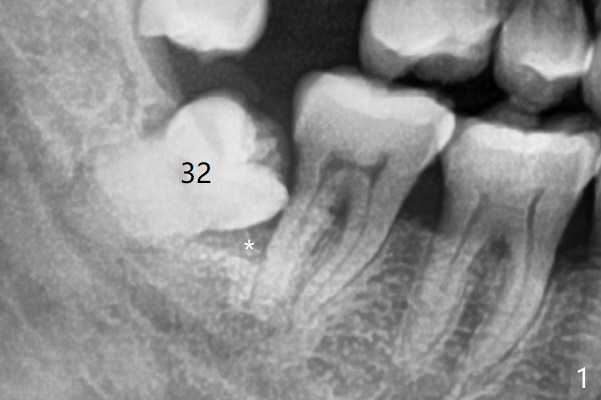

为了顺利成骨(与方炳忠医生根管治疗之后调整咬合一致),拔除智齿前,对第二磨牙近中颊侧咬合面进行降低(图二:箭头)。为了止血和减少骨粉使用量,牙槽窝远中放置胶原骨(Osteogen Plug,O),而第二磨牙远中放置粘性骨粉(sticky bone (allograft),S),后者也是必须的,因为在炎症期间,拔除智齿,出血,即使不严重,一般骨粉容易被血冲走。下次植骨前牙槽窝必须放置含肾上腺素纱布止血,上面加干纱布。最后牙槽窝表面放置两块PRF膜(P),严密缝合。